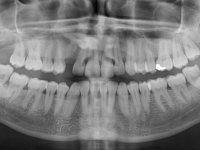

Female patient, 43 years old, non-smoker. Showed an edentulous space in the upper right canine area, resulting from tooth 1.3 impaction. The space had a mesio-distal diameter reduced to the normal size of the upper canine. This is consistent with the presence in the arch of the deciduous canine up to two years ago). Orthopantomography allows clearly view of tooth 1.3 impaction.The patient has a thick gingival phenotype and tolerable oral hygiene.